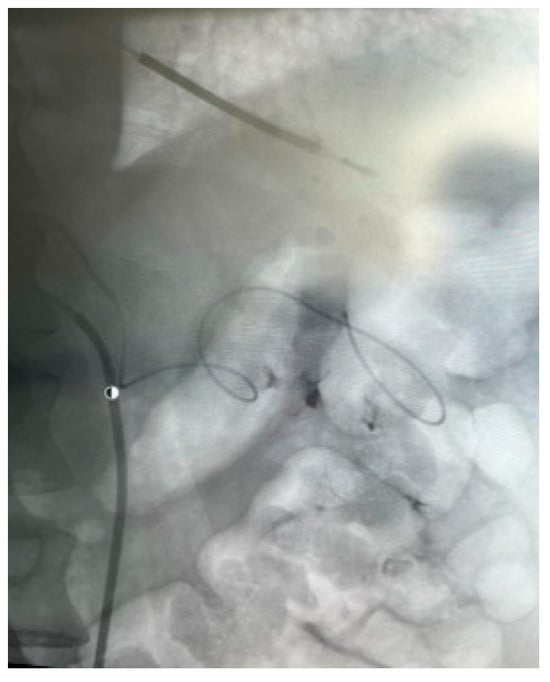

Appendix A.4. Clinical Case 4: Onyx Use in Endoleak Type 1 Excision Post EVAR ABI